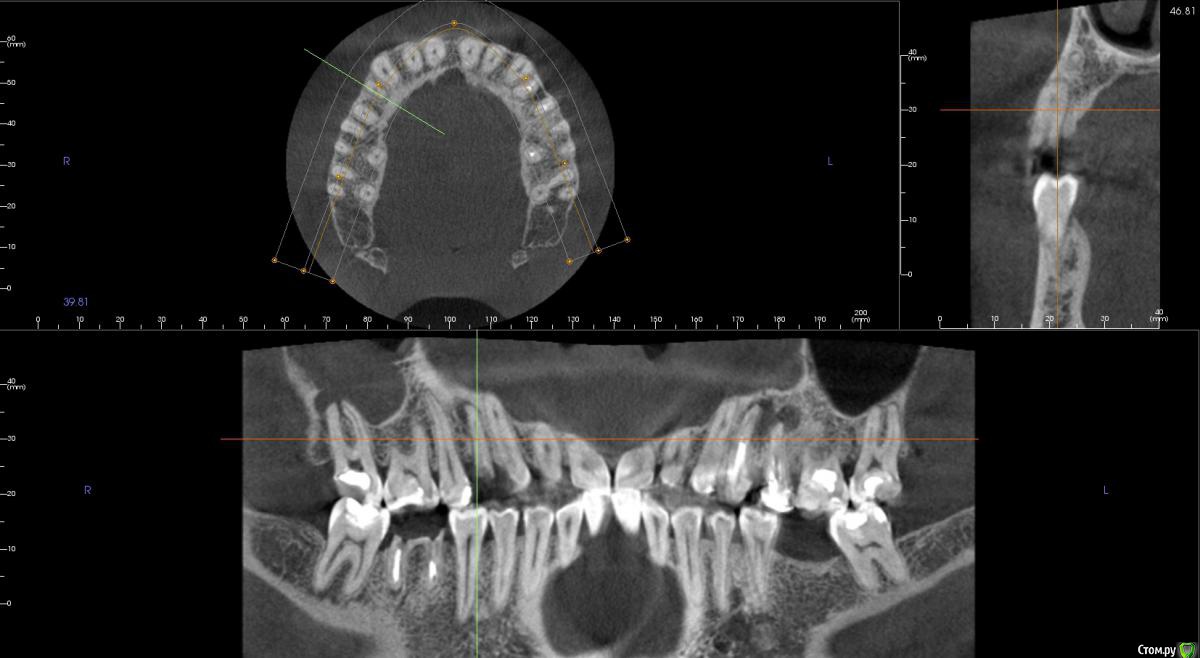

kamranchick Опубликовано 5 ноября, 2015 Поделиться Опубликовано 5 ноября, 2015 Добрый день уважаемые форумчане)Хочу посоветоваться с Вами.Пациент обратился по поводу 14 зуба, хочет удалить и поставить имплантатаБыло предложено идти но одномоментную имплантацию.Вопрос - есть ли противопоказание в данном случае? нужно ли аугментация?Я рассматриваю варианты с устновкой имплантата ALpha Bio SPI 3.3 -13мм, и установка формика с шашлычком(так как бугры хорошие), при условии хорошего торкаВаши советы... Ссылка на комментарий

ПалСаныч Опубликовано 8 ноября, 2015 Поделиться Опубликовано 8 ноября, 2015 Отличный пример под мой вопрос: в области верхушки очаг хронического воспаления, если гранулема уйдет целиком, то ладно; а если удалить корень без нее, то хоть как там кюретируй, нотгарантии что все выудил нет, да и лунка в апикальной трети сплющена. Ставить можно? Или риск нагноения высок? Ссылка на комментарий

faity Опубликовано 10 ноября, 2015 Поделиться Опубликовано 10 ноября, 2015 По сути переапикальные изменения обусловленны инфекцией непосредственно в каналах и после удаления причинного зуба, даже при наличии остаточной МО в костной ткани это никак не мешает приживлению импланта.Но к сожалению мои выводы основанны исключительно на литературных данных в этой области, т.к. я не дядя Карен и не имею возможности проводит гистологические исследования По топику: апекс импланта я бы немного вестибулярнее расположил, чтобы шахта выходила на бугры, а не на вестибулярную стенку и по длине такой, чтобы якорнулся в кости хотя бы на 1 мм Ссылка на комментарий

kamranchick Опубликовано 10 ноября, 2015 Автор Поделиться Опубликовано 10 ноября, 2015 По сути переапикальные изменения обусловленны инфекцией непосредственно в каналах и после удаления причинного зуба, даже при наличии остаточной МО в костной ткани это никак не мешает приживлению импланта.Но к сожалению мои выводы основанны исключительно на литературных данных в этой области, т.к. я не дядя Карен и не имею возможности проводит гистологические исследования По топику: апекс импланта я бы немного вестибулярнее расположил, чтобы шахта выходила на бугры, а не на вестибулярную стенку и по длине такой, чтобы якорнулся в кости хотя бы на 1 ммПридется выбирать. либо идти по небной стенке, либо в правильной ортопедической позиции, а можно ли сразу 2 зайца убить в данном случае? боюсь при удалении дефект будет большим. Ссылка на комментарий